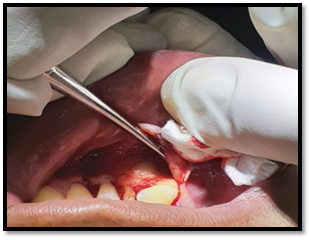

Incisión: Neumann Parcial con bisturí, hoja de bisturí # 15 con un mango de bisturí #3, con la descarga o liberatríz hacia el órgano dentario #3.2 hasta distal del órgano dentario # 4.4.

Levantamiento del colgajo: Se realizó el levantamiento de las papilas y el colgajo mucoperióstico.

Imagen 6. Incisión.

Imagen 7. Levantamiento del colgajo.